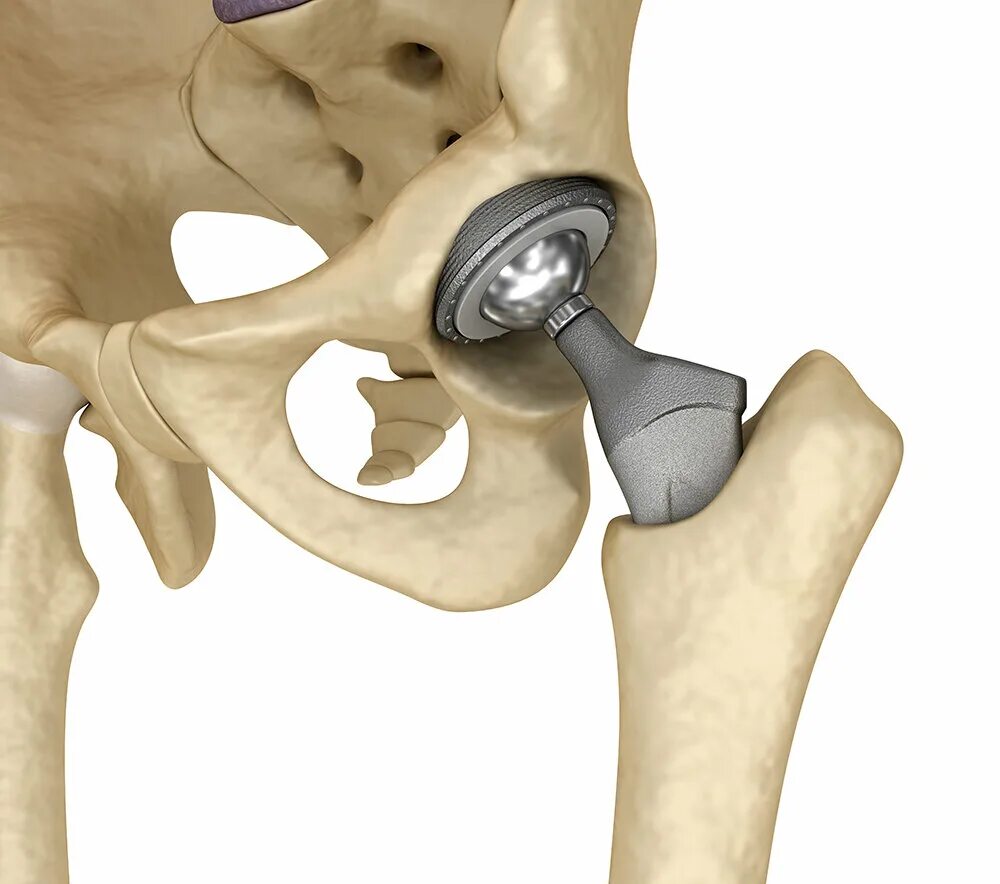

Можно ли лечить тазобедренный сустав